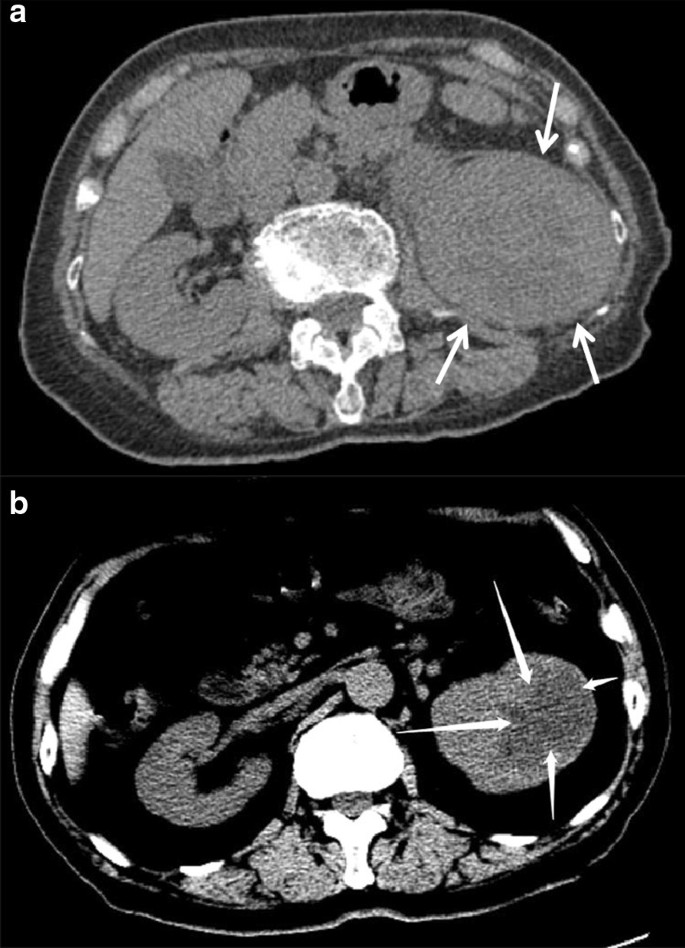

Collecting Duct Carcinoma Radiology Collecting Duct Carcinoma Radiologie Kenmerken

Diagnostische radiologie bij collecting duct carcinoma toont infiltratieve tumoren vooral in de nierschedel, met variërende grootte en locaties.